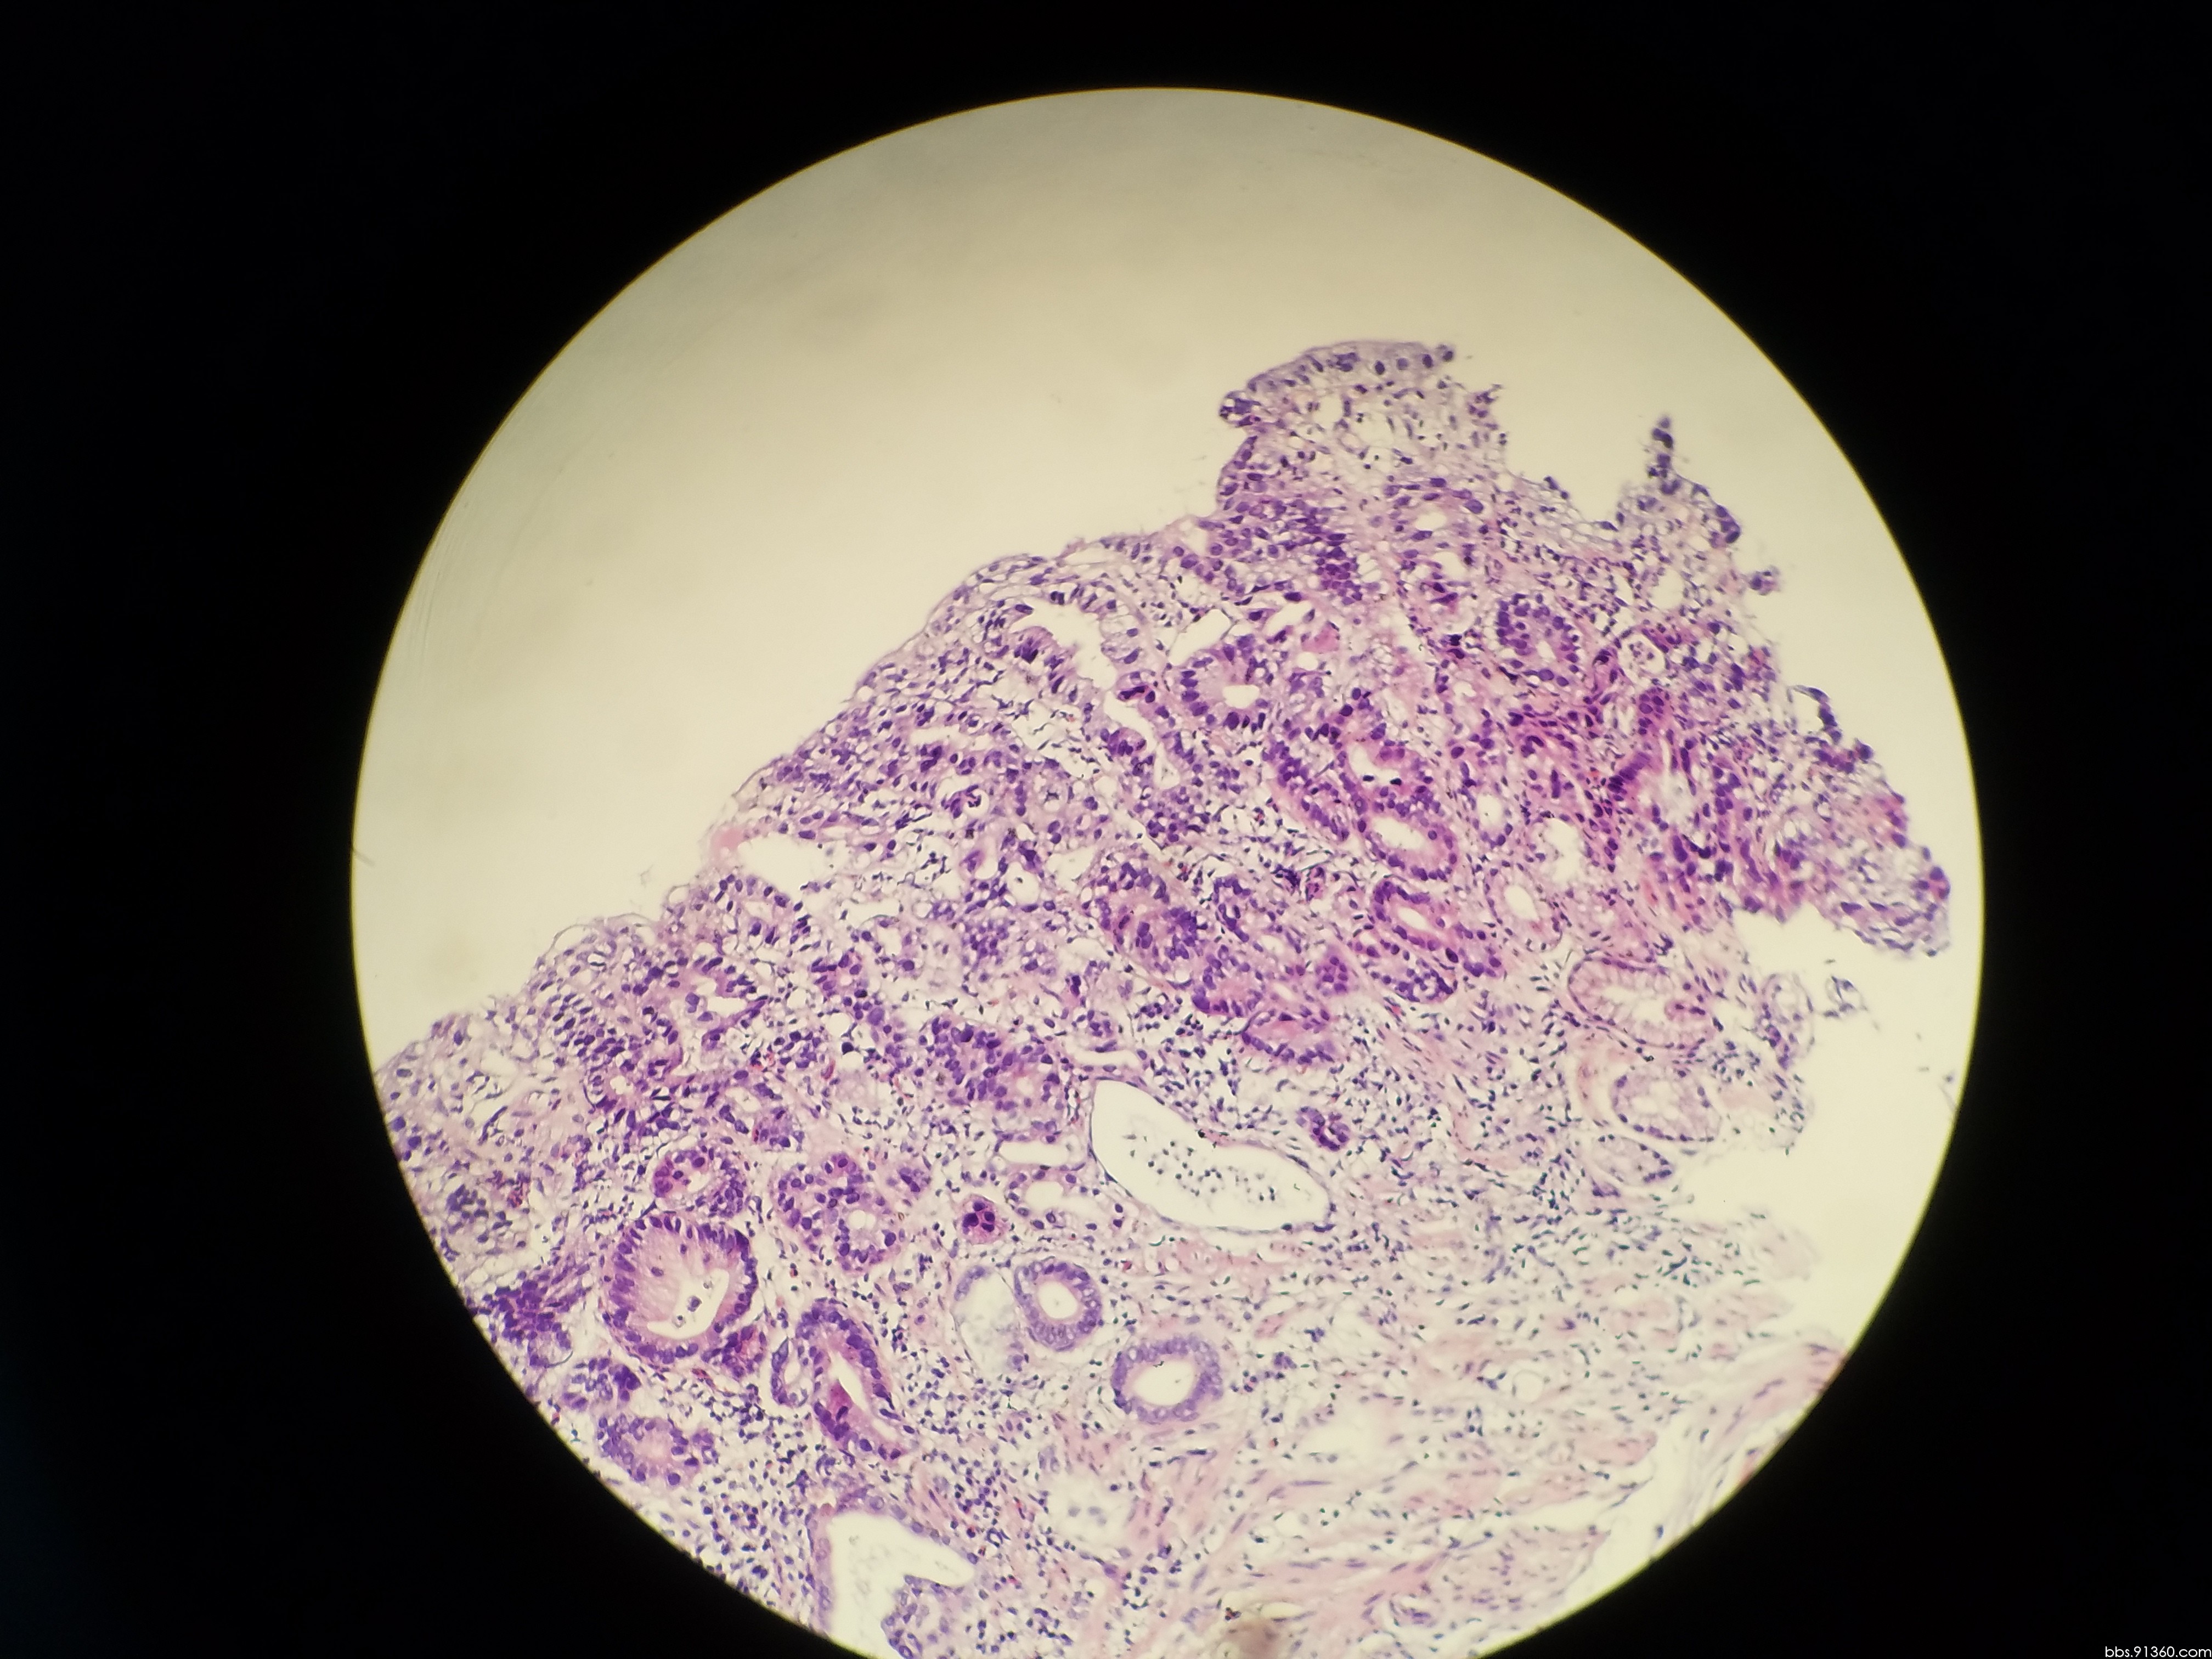

胃窦部黏膜组织活检镜下如图所示胃黏膜发生的有关病变的描述

胃窦部黏膜组织活检镜下如图所示胃黏膜发生的有关病变的描述错误的是

胃窦部黏膜活检

胃窦部黏膜活检

胃窦部黏膜活检

胃窦部黏膜活检